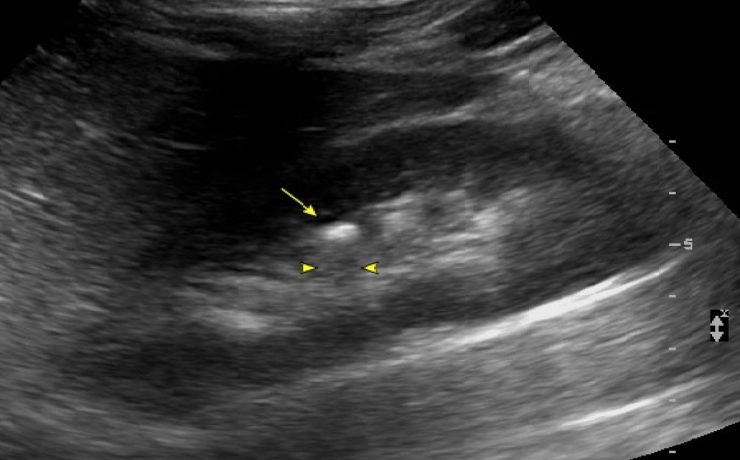

Defectos de la pared abdominal. Estudio comparativo entre onfalocele y gastrosquisis

El onfalocele y la gastrosquisis son los defectos de la pared abdominal, de tamaño variable, que se ubica en directa relación con el cordón umbilical, que contiene asas intestinales y a veces otros órganos como parte del hígado, recubiertos por amnios en la superficie externa, peritoneo en la superficie interna,